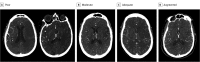

Main outcomes and measures: ASPECTS were evaluated. The adequacy of leptomeningeal collateral blood flow was rated as no or poor, decreased, adequate, or augmented per the adapted Maas scale. The main outcome was an ASPECTS decay, defined as an initial ASPECTS of 6 or higher worsening between RH and TCSC CTs to a score of less than 6 (making the patient less likely to derive clinical benefit from thrombectomy at arrival).

Results: A total of 316 patients were included in the analysis (mean [SD] age, 70.3 [14.2] years; 137 [43.4%] female). In multivariable models, higher National Institutes of Health Stroke Score, lower baseline ASPECTSs, and no or poor collateral blood vessel status were associated with ASPECTS decay, with collateral blood vessel status demonstrating the highest adjusted odds ratio of 5.14 (95% CI, 2.20-12.70; P < .001). Similar results were found after stratification by vessel occlusion level.